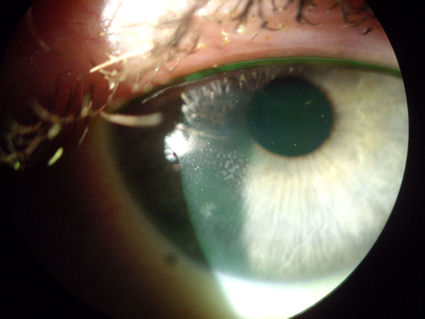

На фотографии ниже представлена роговица пациента, перенесшего операцию LASIK в 2007 году. Эта роговица чрезвычайно сухая и неправильной формы. Кроме того, эпителиальные клетки с внешней поверхности роговицы проникли под лоскут LASIK и выросли под ним. С 5:00 до 8:00 часов клетки можно увидеть в виде белой линии, идущей от нижней части роговицы. Пациент носит специальную газопроницаемую склеральную линзу для защиты травмированной ткани роговицы. Нажмите на изображение, чтобы увеличить.